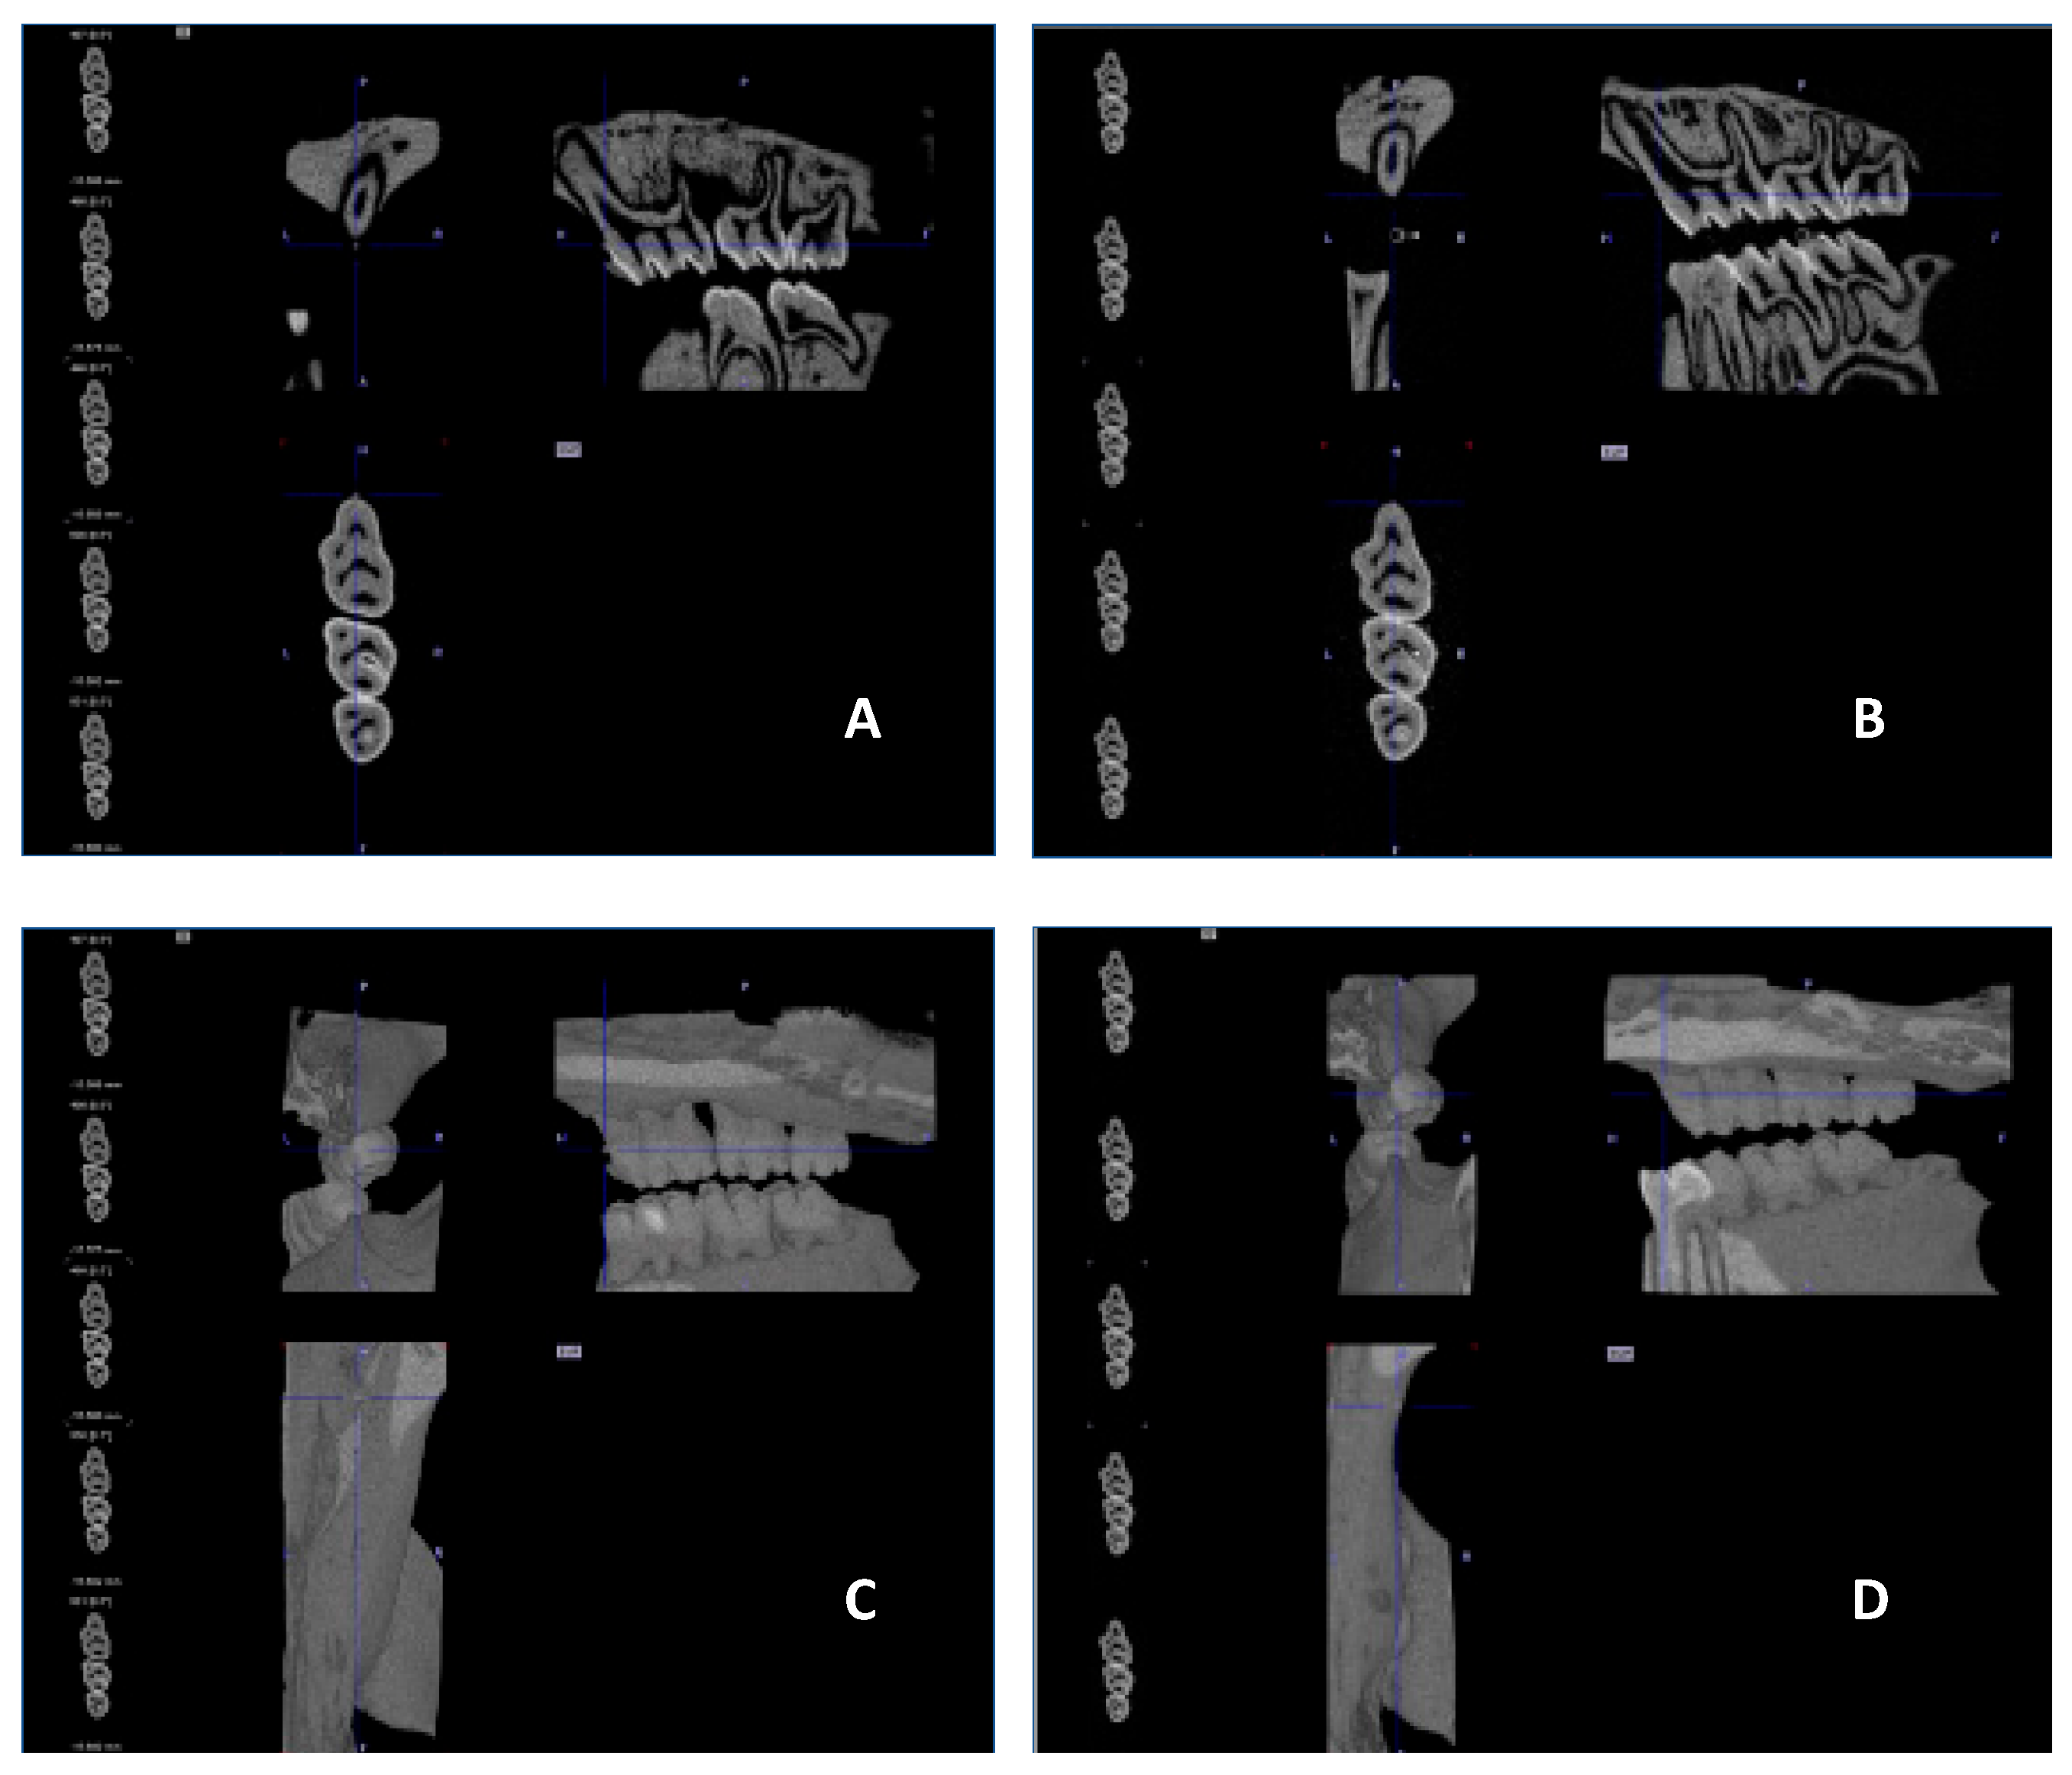

No visible changes were noted in the periodontium. Furthermore, CT scans revealed no alterations in the jawbone area. Due to technical constraints, the experiment was confined to the upper jaw, and alveolar bone loss was quantified using micro-computed tomography (μCT). Measurements were taken from the cemento-enamel junction (CEJ) to the alveolar bone crest (ABC). For each analyzed rat (23 in total), 12 measurements were conducted: three times per molar at two sites (left and right), doubled for statistical replication. The specific distances utilized for statistical analysis are detailed in Figure 8.

Figure 9 presents a representative CT analysis of bone loss in P. gingivalis-infected animals (both minocycline-treated and controls. The beneficial effect of the treatment is clearly visible with regard to bone loss. Comparison of the CEJ-ABC distance shows a significant bone loss, in the non-treated animal (A+C, PG), which was remarkably diminished by the treatment (B+D, PG+MIN-T).

Micro-computed tomography analysis

To determine bone loss High Resolution Animal Computed Tomography (Micro-CT, MILabs, Netherlands) was used. All animals were scanned at two time points (before treatment (T0) and on the day of termination of the experiment (TEND)). Imaging was performed at an ultra-focus magnification, 50kV source voltage and 0.21 mA current. Three-dimensional images were obtained using the PMODE software (Switzerland). To assess the alveolar bone loss, a linear distance from CEJ to ABC of each tooth of the lower and upper jaw was measured. Each measurement was performed 3 times, and the data are presented as the mean ± standard deviation (SD). The results are presented as the distance after subtracting the basal measurement (T0) from the measurement obtained at the endpoint of the procedure (TEND).

Figure 8. Overview of the measured distances used for the statistical calculations. The three upper molars are marked with 1, 2 and 3. The distances are marked as yellow lines in red borders. This example is taken from the P.gingivalis infected, but not treated group (PG).

Figure 9. µCT images showing the treatment effect of the novel formulation against a P.gingivalis infection in the rat ligature model. [A] and [B] sagittal section of the head/jaw axis at the level of the bone/teeth [C] and [D] sagittal section of the head/jaw axis (the same scan) after adding bone and tissue mass [A] and [C] infected and untreated animals (PG), [B] and [D] infected and treated animals (PG+MIN-T).